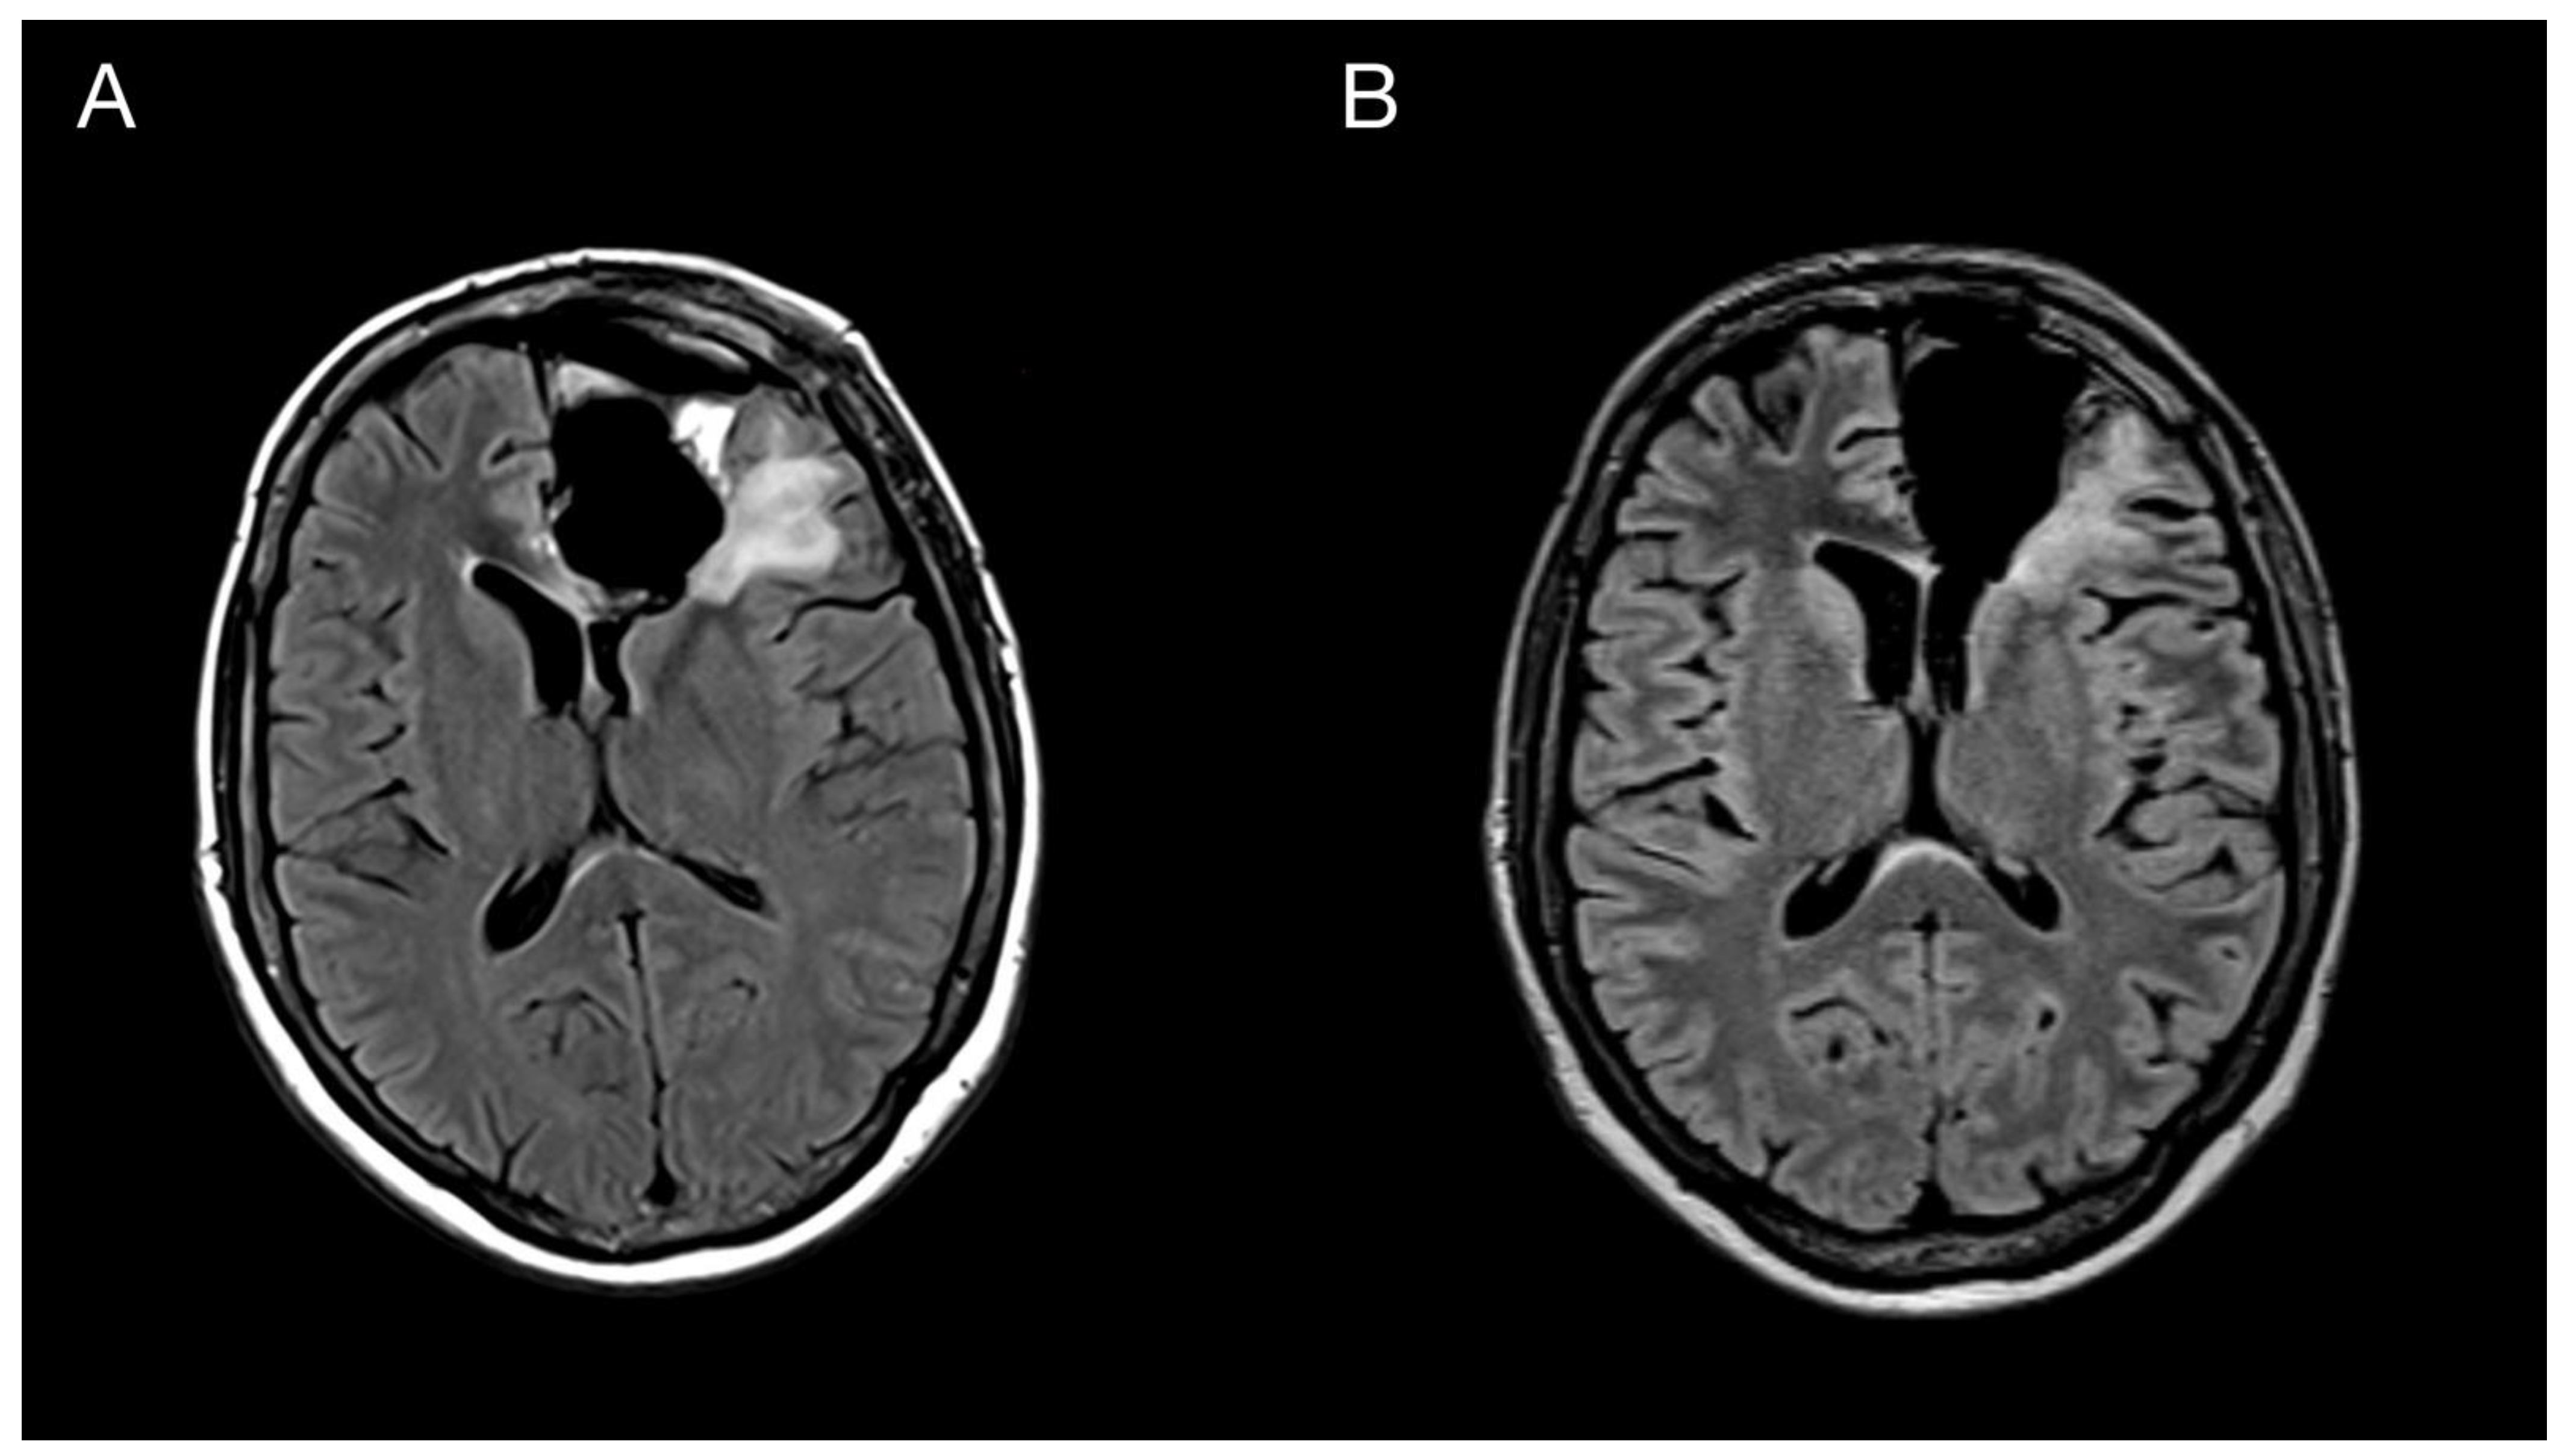

Figure 5.

Imaging of the primary brain tumor prior to and after the oncological treatment. Axial brain MRI (fluid-attenuated inversion recovery images) prior to oncological treatment displaying GBM’s rapid early progression in the left frontal lobe (A) and two months after the chemo-radiotherapy (B).